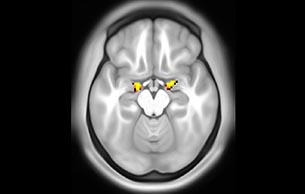

BOLD fMRI activation, depicted in color, of left anterior insula (MNI plane z = 8 mm) in a single subject by a contrast between viewing and matching faces with negative emotion (angry, sad, scared) versus happy faces. The voxelwise threshold is p < 0.001, and colored voxels survive false discovery rate correction to p < 0.05. The activated voxels in color are overlaid on the subject's own 3D-TFE image displayed in grayscale, after transforming the data to MNI space. The fMRI pulse sequence was a single shot FFE echo planar acquisition using MultiBand SENSE factor 6, dS SENSE factor 1, isotropic voxel size 2.4 mm, 60 transverse slices, TR 950 ms, TE 30 ms, flip angle 52 degrees, 517 dynamic scans, total scan duration 8:21 minutes. Image provided by James M. Bjork, PhD, Associate Professor of Psychiatry at VCU.

Emotional n-back task combines a test of working memory with the use of emotive (faces) and neutral (places) images. The contrast in the images is between the activity when faces are presented compared to places, showing activation in the amygdala, fusiform, and occipital face areas.

Processing based on the Human Connectome Project (HCP) pipelines. The high resolution of the fMRI data allows extraction of the cortical surface, with minimal averaging of non-cortical signal. Surface based analysis provides improved cross-subject alignment, and prevents signal contamination between adjacent sulci.

Group analysis of 88 9- and 10-year olds part of ABCD, all scanned at UVM on Philips Achieva 3.0T dStream. Scale runs from red p=0.001 to yellow p<10ˆ-5. Images provided by Dr. Watts.

Acquisition using the ABCD protocol for fMRI with TR 800 ms, TE 30 ms, flip angle 52°, 2.4 mm isotropic imaging resolution with a 216×216×144 mm3 field of view using a MultiBand acceleration factor of 6 (60 slices, no gap). Two runs of 5 minutes per subject.